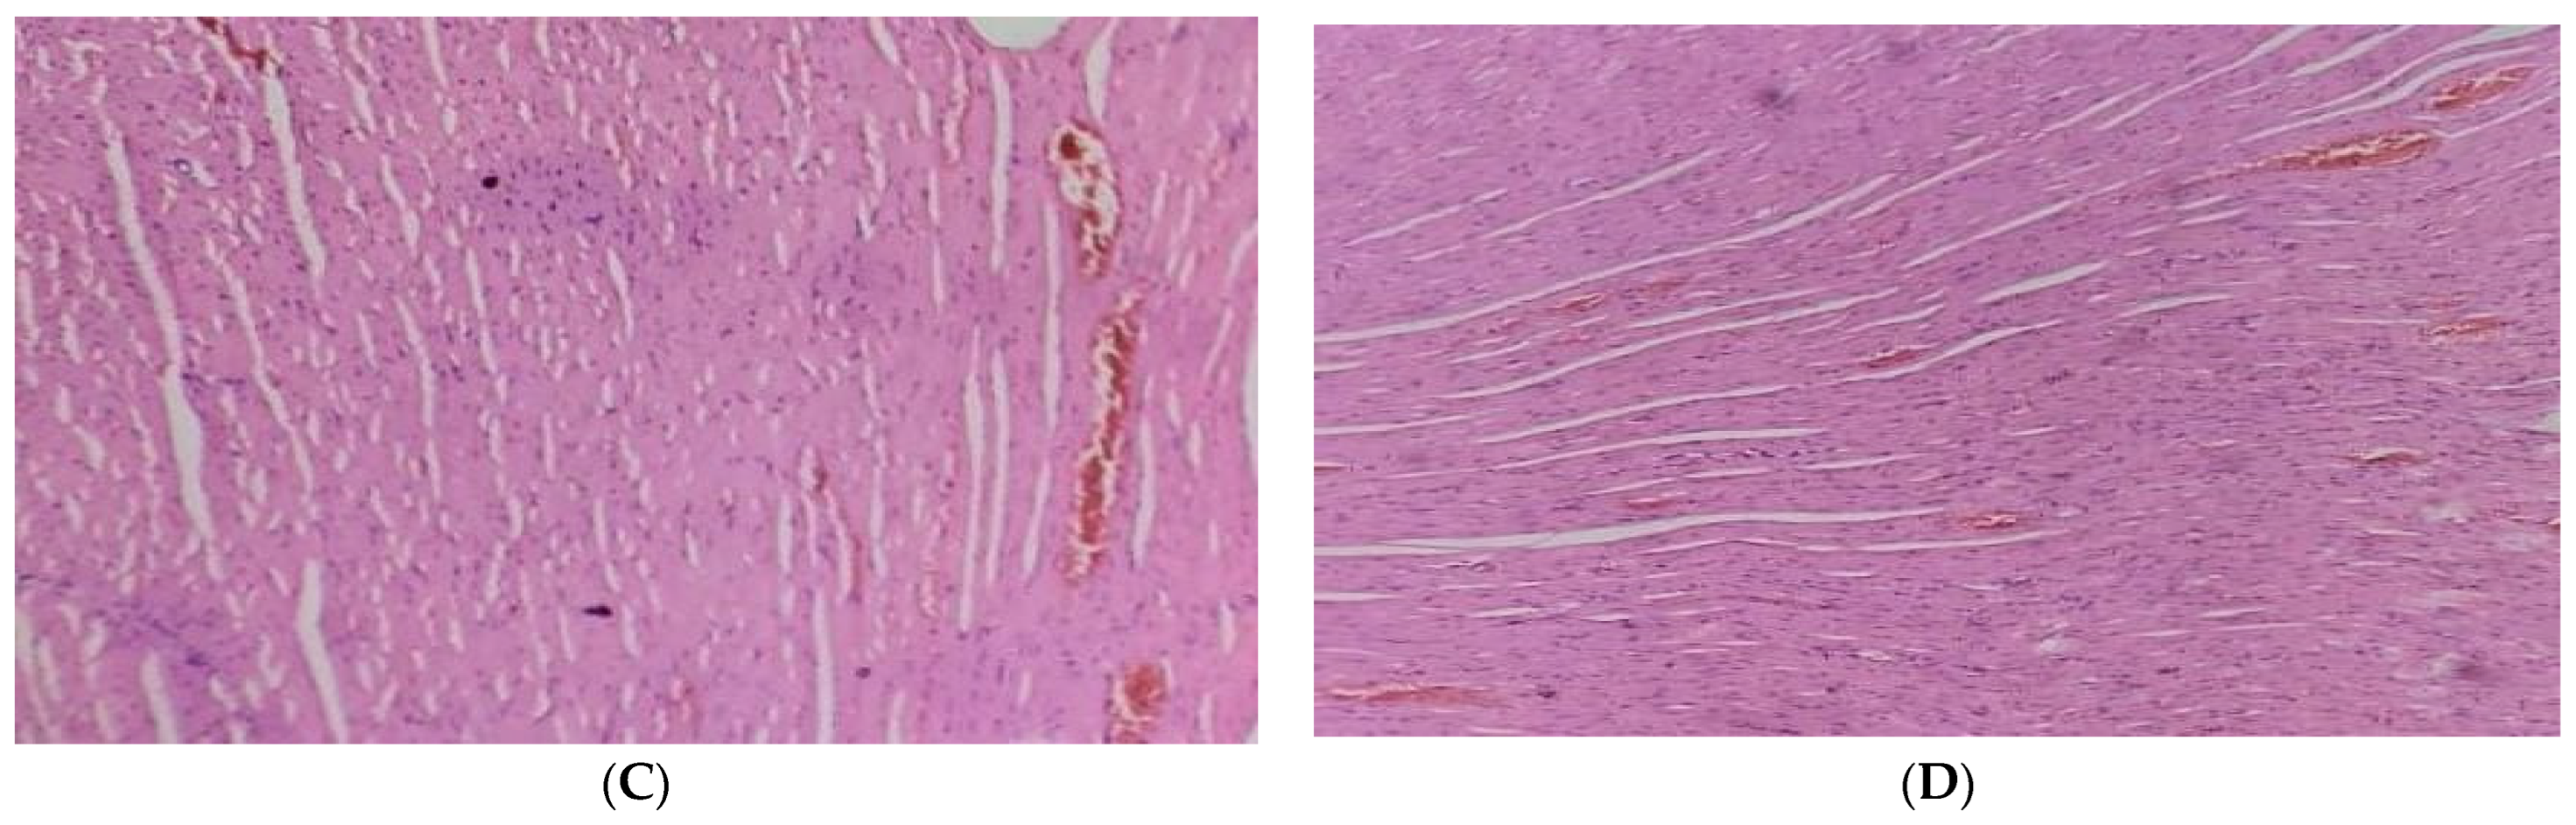

Heart

According to the findings, contrary to the normal architecture seen in the hearts of the normal control group, histological analysis of the diabetic cardiac tissues revealed fibrosis, degenerating muscle fibers, and disrupted muscle fibers with extravagated blood. In the diabetic rats given 250 mg/kg of the JSP extract, small patches of widely separated myofibrils and virtually normal myocytes were seen. Although, the diabetic group treated with 500 mg/kg showed specific improvements (p < 0.05) near normal myocytes, a lesser degree of myocardial damage, and a significant reduction in myocardial edema (Figure 4).

Figure 4.

(A) Cardiac tissue of the normal control group with normal histology of cardiac myofibril. (B) Diabetic cardiac tissue showed fibrosis and disrupted and degenerating muscle fibers with extravagated blood vessels. (C) Cardiac tissue of the 250 mg/kg-treated group with partial improvement of disrupted elastic fibers and enlarged myofibrils. (D) Cardiac tissue of the 500 mg/kg-treated group showed reversal of cardiac injury with a lesser degree of myocardial damage and mild edema.